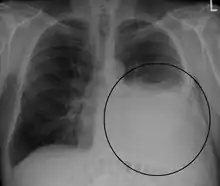

A pleural effusion appears as an area of whiteness on a standard posteroanterior chest X-ray.[12] Normally, the space between the visceral pleura and the parietal pleura cannot be seen. A pleural effusion infiltrates the space between these layers. Because the pleural effusion has a density similar to water, it can be seen on radiographs. Since the effusion has greater density than the rest of the lung, it gravitates towards the lower portions of the pleural cavity. The pleural effusion behaves according to basic fluid dynamics, conforming to the shape of pleural space, which is determined by the lung and chest wall. If the pleural space contains both air and fluid, then an air-fluid level that is horizontal will be present, instead of conforming to the lung space.[13] Chest radiographs in the lateral decubitus position (with the patient lying on the side of the pleural effusion) are more sensitive and can detect as little as 50 mL of fluid. Between 250 and 600mL of fluid must be present before upright chest X-rays can detect a pleural effusion (e.g., blunted costophrenic angles).[14]

Massive left-sided pleural effusion (whiteness) in a patient presenting with lung cancer.